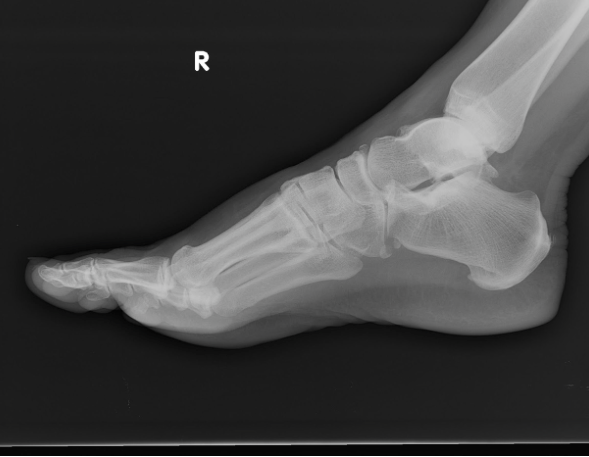

What is this?